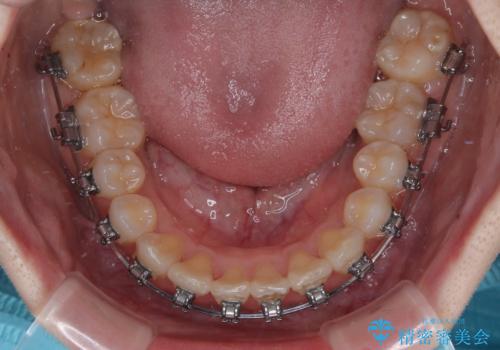

- メタルブラケット

右上と左下の第一大臼歯2本が周辺の歯と比べて位置がずれていたため、ゴムかけやワイヤーに曲げを入れることで移動を試みましたが、どうよら癒着をしており、移動困難と判断されました。

見た目や咬み合わせに違和感がないとのことで、癒着歯の無理な移動は試みずに治療を終えることとしました。